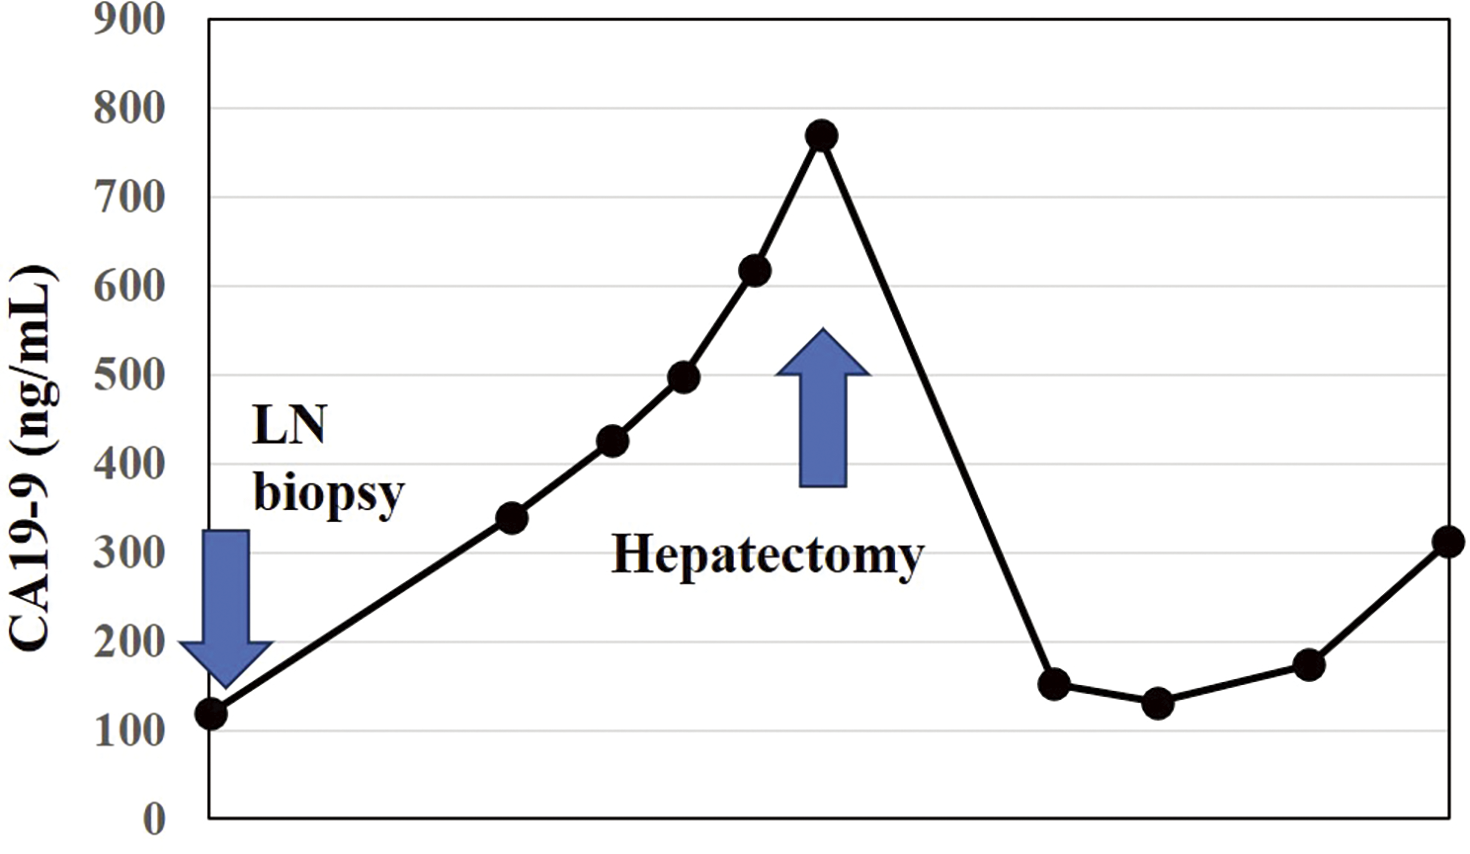

The patient is a 74-year-old man who had surgery for cervical esophageal cancer 2 years ago. The final diagnosis was moderately differentiated squamous cell carcinoma (SCC) with LN metastasis, pT3N1M0 pStage III. Chemoradiotherapy was performed and there was no recurrence of the esophageal cancer. During follow-up, a low-density lesion, a diameter of 15 mm, was detected in segment 4 of the liver by CT (Fig. 1A). The tumor was located just adjacent to the umbilical portion. There were some swollen LNs in the anterior mediastinum (Figs. 1B and 1C). The accumulation of FDG was also detected in the hepatic lesion (standardized uptake value; SUVmax: 8.4) and the anterior mediastinal LN (SUVmax: 11.1) by PET (Fig. 1D). Needle biopsy was performed for the liver tumor and the diagnosis was ICC (Figs. 2A and 2B). The elevation of the serum level of carbohydrate antigen 19-9 (CA19-9) was detected and its level was 119 ng/mL. The levels of carcinoembryonic antigen (CEA) and SCC were within normal range. To confirm the diagnosis of the swollen LNs in the anterior mediastinum, an excisional biopsy was performed. In the operation, there were several firm LNs pulpable just behind the sternum. According to the pathological findings, the tumor in the LN was an intermediate differentiated adenocarcinoma. Atypical cells with increased nuclear chromatin and enlarged nuclei were proliferating and forming glandular structures (Figs. 2C and 2D). The structure of the tumor in the LN was similar to that of the hepatic lesion. Immunohistochemistry showed that the tumor was positive for CK7 and CK20, weakly positive for MUC5AC, but negative for CDX-2, Napsin, TTF-1, and p40 (Fig. 3). The final diagnosis was the lymphatic metastasis from ICC. As the diagnosis of distant metastasis (Stage IVB), the chemotherapy using Gemcitabine, Cisplatin, and Durvalumab was performed for 8 courses. The new lesion appeared just next to the main tumor in S4 (Fig. 4) and the elevation of CA19-9 was also observed (Fig. 5). We could not detect any swollen LNs in the anterior mediastinum by PET or CT. In addition, it was difficult to continue the chemotherapy due to the renal dysfunction. As the tumors were located in the left lobe of the liver, a left hepatectomy with LN dissection was performed. In the operation, there were multiple intrahepatic metastatic lesions limited to the left lobe of the liver. Grossly, the lesion corresponds to a mass-forming type with a central necrotic area and several satellite nodules (Fig. 6). The size of the main tumor was 30 mm in diameter. Most of the tumor cells were viable and they showed serosal and neural invasion around the portal vein (S1, Vp1, Vv0, and Va0). There were no metastases in the regional LNs. Although re-elevation of CA19-9 is observed after hepatectomy (Fig. 5), the patient does not have any recurrence for 9 months after hepatectomy.

Fig. 5

Transition of CA19-9.